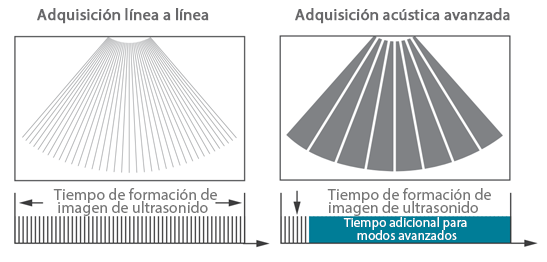

Desde que se fundó la compa?ía, Mindray ha explorado incansablemente nuevas formas de mejorar la confiabilidad del diagnóstico. Con la revolucionaria tecnología de ZONE Sonography?, la nueva plataforma ZST+ de Resona?7 lleva la calidad de la imagen por ecografía a un nivel superior mediante el procesamiento de datos de canal y la adquisición de zona.